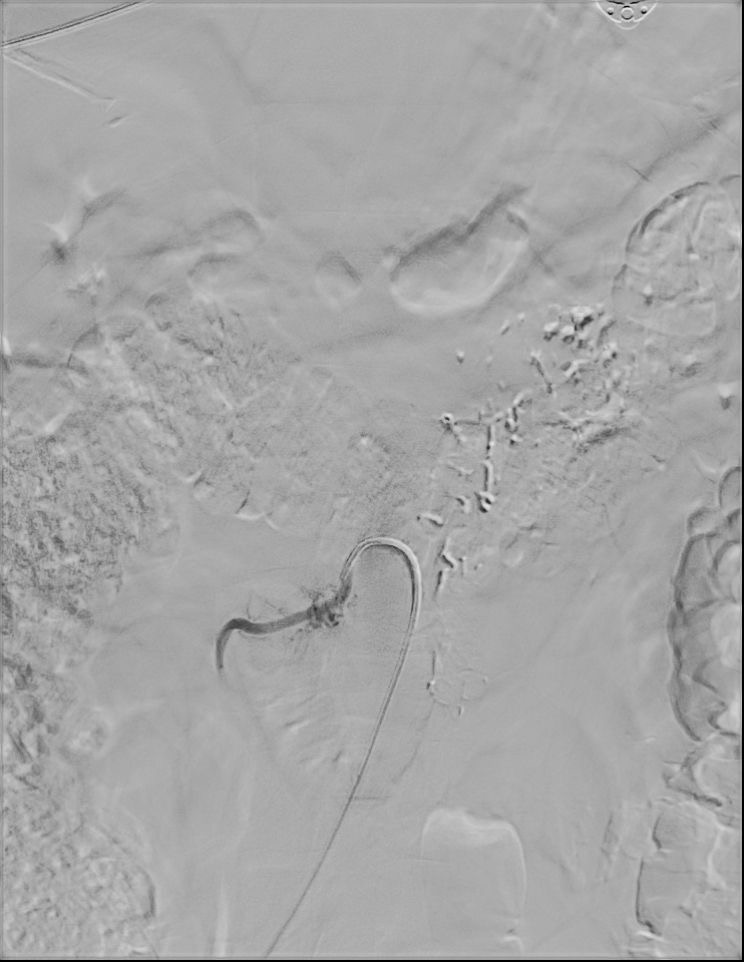

W przypadku prezentowanej pacjentki nie stwierdzono objawów neurologicznych poza bólem głowy. Po wstępnej diagnostyce została przekazana do Oddziału Neurochirurgicznego Szpitala Kopernika w Łodzi. W trybie pilnym wykonano angiografię cyfrową (DSA), która precyzyjnie uwidoczniła AVM.

Przeprowadzono embolizację części tętnic zaopatrujących AVM, co zmniejszyło ryzyko krwawienia śródoperacyjnego. Następnie wykonano kraniotomię podpotyliczną lewostronną z całkowitym usunięciem malformacji. Zabieg przebiegł bez powikłań, po zabiegu u pacjentki nie stwierdzono deficytów neurologicznych. Kontrolna angiografia potwierdziła całkowite usunięcie zmiany, co pozwala uznać pacjentkę za wyleczoną.

W badaniu angiografii subtrakcyjnej widoczne jest rozległe (ponad 3 cm) gniazdo naczyniowe zaopatrywane z tętnicy przedniej mózgu prawej, zarówno z gałęzi okołospoidołowej, która oddawała 2 tętnice żywiące, jak i gałęzi korowych, oddając jedno naczynie żylne drenujące do zatoki strzałkowej górnej.